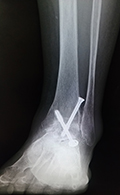

変形性足関節症

変形性足関節症は、足関節の表面に覆われている軟骨がすり減ってしまう疾患です。骨折や繰り返す捻挫など外傷によって起こることが多いと言われています。

痛みが強い場合や変形が強い場合は、主に関節固定術を行います。適応となる患者さんは限られていますが、足関節の可動域を温存するため、脛骨低位骨切り術や人工足関節置換術を行うこともあります。

●負担を小さくする関節鏡下関節固定術

当院では、膝関節や股関節などの下肢全体のアライメントを含めて、痛みの原因を追究し、手術療法を決めるようにしています。従来は足関節前方を大きく切開して行う方法が行われていましたが、手術後の痛みや傷が大きくなることが問題でした。当院では患者さんへの侵襲を減らすため、皮膚切開を大きく行わない関節鏡視下関節固定術を積極的に導入しています。

単純レントゲン写真

(矢印)